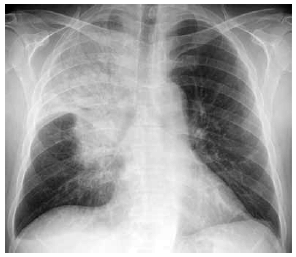

Paciente é atendido com quadro de febre, dispneia, tosse e expectoração amarelada há 5 dias. Não há antecedente mórbido relevante. Ao exame físico: PA: 88 x 58 mmHg, FC: 132 bpm, FR: 46 ipm, T: 38,8 ºC e SatO2: 72%. Eletrólitos e função renal: normais. A radiografia realizada é mostrada a seguir.

Em relação à insuficiência respiratória aguda, a conduta imediata recomendada é